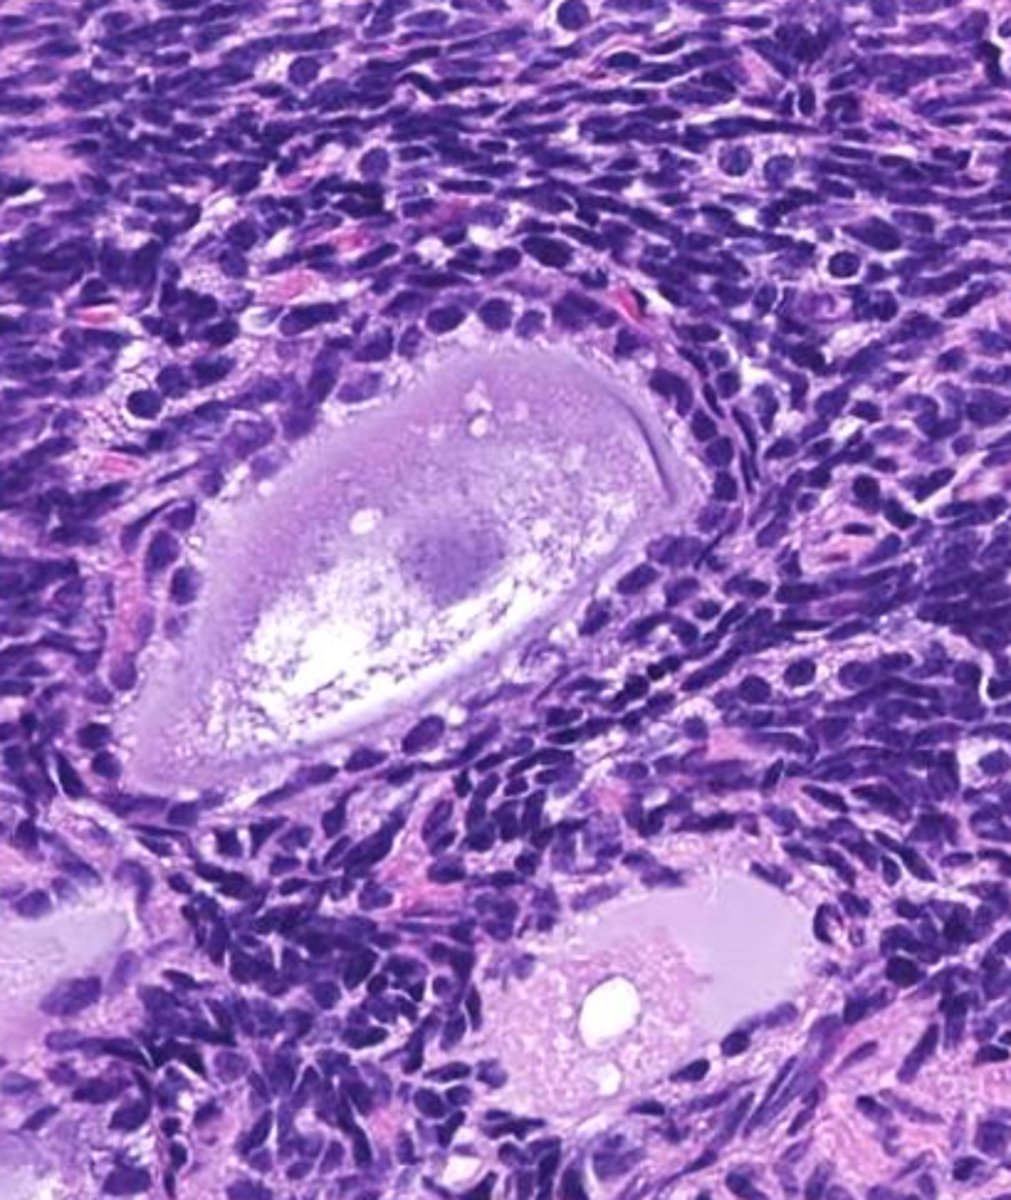

tertiary

this is a _____ follicle

antrum

the fluid filled space, marked by the X, is called the _____

cumulus

the yellow cells surrounding the oocyte in the antral follicle are called ____ cells

Graafian

antral follicles, or tertiary follicles, are also called ______ follicles

theca cells

yellow

green

granulosa cells

pink

orange

oocyte

red

cumulus oophorus

a mound of granulosa cells that covers the oocyte and secures it to the follicle wall (yellow)